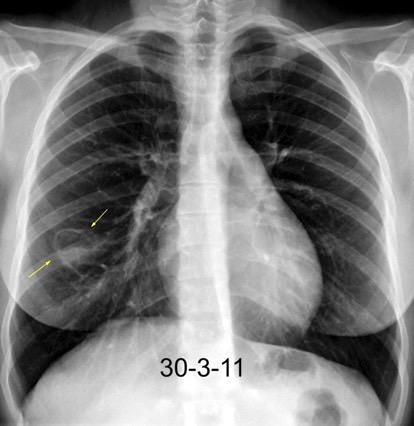

Nódulos pulmonares múltiples. (flechas verdes). Masas paratraqueales. (flechas amarillas). Dudoso ensanchamiento retrocrural (flechas negras). sigue….

Ttawfik A et al. Trans-diaphragmatic Pathologies: Anatomical Background and Spread of Disease on cross-sectional Imaging. Current Problems in Diagnostic Radiology. 2021.

T. mixto de células germinales del testículo

izquierdo Metástasis pulmonares. (flechas verdes). Ganglios paratraqueales. (flechas amarillas). Ganglios retroperitoneales (flechas negras)

Tawfik A et al. Trans-diaphragmatic Pathologies: Anatomical Background and Spread of Disease on cross-sectional Imaging. Current Problems in Diagnostic Radiology. 2021.